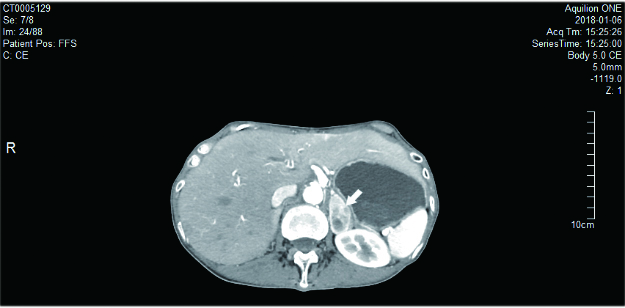

患者2,女,73岁,因“发现血糖升高13年,反复心悸出汗1年”入住我科。入院后监测血糖波动于3.2~22.6 mmol/L,血压波动于77~223/38~90 mmHg。尿VMA 88.20μmol/24h(0.1-68.6)。腹部CT:左侧肾上腺见一不规则肿块,大小35.3 mm×19.9 mm×29.4 mm,考虑嗜铬细胞瘤(图 3)。术前予特拉唑嗪口服4周,血压控制基本平稳。术前24 h血压波动在99~134/55~66 mmHg。手术当日停用特拉唑嗪,全麻下行腹腔镜左肾上腺肿瘤切除术。术中治疗监测血压波动于110~166/42~69,手术过程顺利,持续约50 min,术中出血约10mL。术后转入重症监护室。术后7 h出现血压下降,予扩容及血管活性药物维持血压仍偏低,术后10 h复查血常规血红蛋白45 g/L,较前明显下降,超声提示腹腔内大量积血。考虑腹腔大量出血,行腹膜后探查+血肿清除止血术,术后血红蛋白稳定,血压稳定。手术病理:(左肾上腺)嗜铬细胞瘤。出院时血压126/70 mmHg左右,未使用降压药物。予甘精胰岛素、阿卡波糖及西格列汀控制血糖,血糖控制在8~10 mmol/L左右。

| 图 2 腹部CT:左侧肾上腺见一不规则肿块,大小35.3 mm×19.9 mm×29.4 mm(前后×左右×上下),边界清,平扫密度不均,增强扫描明显不均匀强化,中心见不规则囊变坏死区,提示左侧肾上腺占位,考虑嗜铬细胞瘤(箭头) |